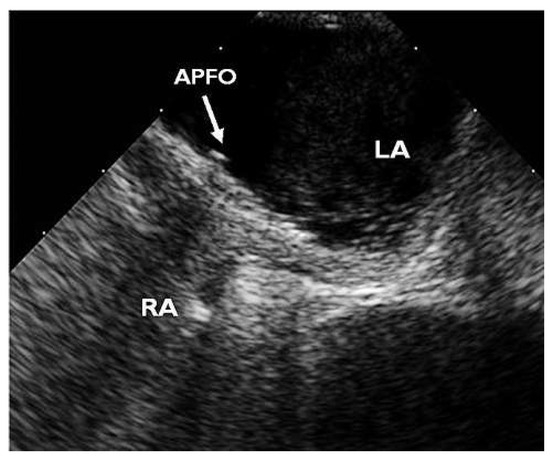

Waiting for Evidence Seems to Make Sense—Except for the One Providing the Evidence

by Thomas Pilgrim, Rolf Vogel and Bernhard Meier

Cardiovasc. Med. 2012, 15(9), 258; https://doi.org/10.4414/cvm.2012.01697 - 26 Sep 2012

A 58-year-old male presented with a history of two prior transient ischaemic attacks and was found to have a patent foramen ovale (PFO) in the absence of atrial fibrillation or relevant carotid atheromatosis. PFO closure was deferred at this stage due to the [...] Read more.

A 58-year-old male presented with a history of two prior transient ischaemic attacks and was found to have a patent foramen ovale (PFO) in the absence of atrial fibrillation or relevant carotid atheromatosis. PFO closure was deferred at this stage due to the lack of clinical evidence. Three years later the patient was re-admitted after a major stroke with residual symptoms and finally underwent PFO closure in a minimally invasive procedure using an Amplatzer PFO Occluder. Full article

Show Figures

Figure 1